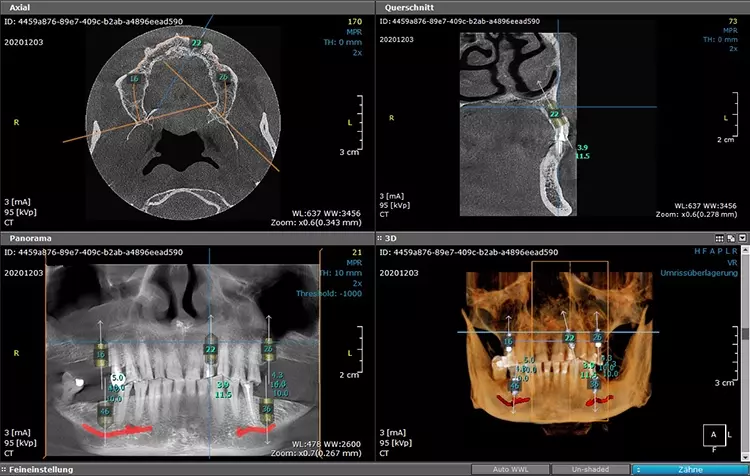

Neugestaltung der Front bei starken Zahnfehlstellungen

Bei dem heute 49-jährigen Patienten wurde seit Kindertagen versäumt, die Ober- und Unterkieferzahnbögen kieferorthopädisch auszurichten. Der Patient leidet seitdem stark unter seinen Zahnfehlstellungen.

Die Fraktur des stark elongierten Zahnes 21 war für den Patienten der Ausgangspunkt, sowohl die Front des Ober- als auch des Unterkiefers prothetisch überarbeiten zu lassen. Dabei wurde der frakturierte Zahn 21 durch ein navigiert eingesetztes Sofortimplantat ersetzt, während die verschachtelt stehenden Zähne 12 und 42 durch eine Brückenversorgung korrigiert wurden (Abb. 4a-j).